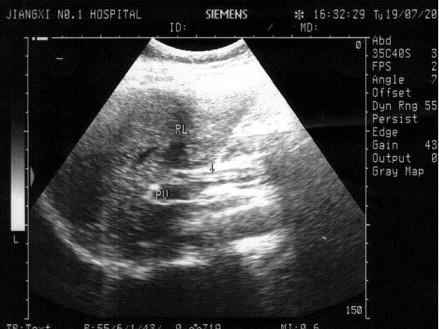

问题 患者女33岁,右上腹剧痛5小时,体检:右上腹压痛及叩击痛(弱阳性),B超检查如图所示,根据超声声像图,诊断为?(?)

选项 A.胆总管结石 B.胆总管引流管回声 C.胆总管蛔虫 D.胆总管胆泥淤积 E.胆总管癌

答案 C